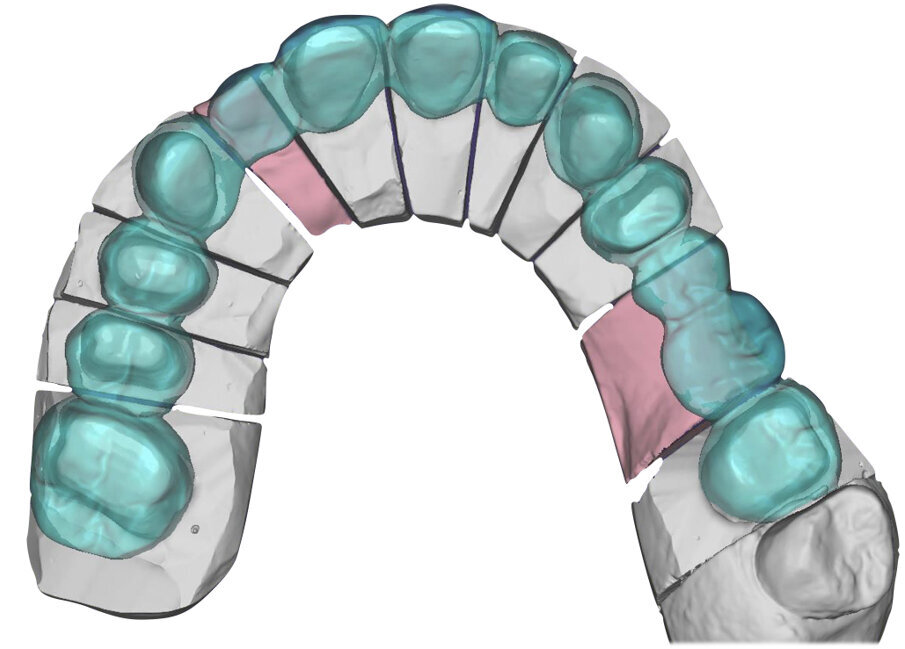

Si esegue perciò cefalometria (Fig. 8) su radiografia latero-laterale (Fig. 9) e axiografia dei movimenti limite (Cadiax Compact, Gamma Dental) (Fig. 10) per la programmazione di un articolatore a valori medi (Artex TR, AmmanGirrbach) e montaggio dei modelli con arco faciale, che confortano nella produzione di un primo provvisorio prelimatura con rialzo arbitrario della VDO di 5 mm sull’asta incisale e miglioramento di OB e OJ, a scopo pre-terapeutico interlocutorio e di immediata risoluzione estetica. Conclusa la necessaria terapia causale e restaurativa viene eseguita la scansione intraorale delle arcate (TRIOS 3 Pod, 3Shape) (Figg. 11-14) e del rapporto articolare con cera di RP (Fig. 15). La scansione è stampata (VisiJet RWT, 3D Systems) con monconi sfilabili tramite stampante 3D (ProJet MJP 2500 Plus, Selltek) (Figg. 16-20), i modelli derivanti sono zoccolati e montati con cere di RP e arco faciale su articolatore a valori individuali (Reference SL, Gamma Dental). La programmazione dell’articolatore derivante dalla registrazione axiografica è ora eseguita come da indicazioni del software (Gamma Dental software, sia per l’uso degli inserti condilari ed incisali, sia per la definizione degli angoli di SCI e di Bennet (Fig. 21). Lo spazio protesico risultante a una VDO adeguata alla riabilitazione dei denti anteriori vitali, con anatomia non ulteriormente modificabile, è insufficiente per uno stabile ripristino dei rapporti occlusali, specie nei tragitti funzionali. Si decide perciò di impiegare due inserti rossi di programmazione di protrusiva (+2 mm) per riposizionare la mandibola in TRP (Figg. 22, 23).

Ciò consente un miglioramento dei rapporti interarcata, un guadagno di spazio protesico in regioni premolari e molari, ed il mantenimento di uno spazio protesico conforme ad una corretta anatomia per i denti vitali da 1.3 a 2.3. Al paziente viene pertanto aggiornato il piano di trattamento e proposta la riabilitazione in TRP, con la previsione di overlays all’arcata inferiore per costruzione del nuovo piano occlusale. In posizione terapeutica sono modellati i coni delle centriche attive sui monconi sfilabili all’arcata inferiore, per la successiva individuazione al CAD con modulo articolatore del piano occlusale studiato. Questo rapporto articolare in TRP è ora scansito con scanner da laboratorio Xanos Evo Scan Compact (Fig. 24).

I modelli sono così importati in corretta posizione spaziale tramite il modulo exocad Virtual Articulator (Fig. 25). Non avendo a disposizione nel CAD l’analogo virtuale dell’articolatore Reference SL, viene impostato il sistema virtuale SAM, che usa lo stesso piano di riferimento axio-orbitale e geometria sovrapponibile al Reference SL. Per la programmazione virtuale dei parametri funzionali dell’articolatore si riesegue l’output dall’axiografia elettronica con Gamma Dental per SAM (Fig. 26). Si procede perciò ora con la modellazione CAD della ceratura mantenendo il riferimento dato dal piano occlusale individuato dai coni di centrica scansiti con l’articolatore (Fig. 27). L’articolatore virtuale consente una prima verifica dei rapporti occlusali tra gli elementi e un abbozzo di funzionalizzazione delle cuspidi con strumenti virtuali dinamici, che permette di arrivare ad un CAD design vicino alla morfologia ricercata (Figg. 28-33). Il modellato è ora fresato in cera Yeti Dental al CAM con fresatore VHF Cam5-S1 ed i denti in cera, tutti singolarmente sfilabili, sono posizionati sui modelli eseguiti con stampa 3D.